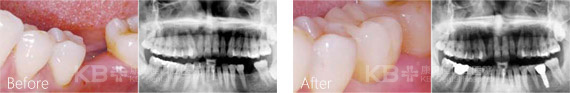

种植牙被誉为人类的第三副牙齿,是以外科小手术的方式植入人工牙根,再在人工牙根上制作烤瓷牙冠。种植牙可以获得与天然牙功能、结构以及美观效果十分相似的修复效果,种植牙已经成为越来越多缺牙患者的优选修复方式。

南京康贝佳口腔种植科主任冯观保介绍,相比于传统种植牙即刻种植无需等待,当天就能戴上牙冠。即刻种植技术具有稳固牢靠、舒适美观、安全快速、不伤健康邻牙等独特优势,是当前采用率较 高的种植方式。